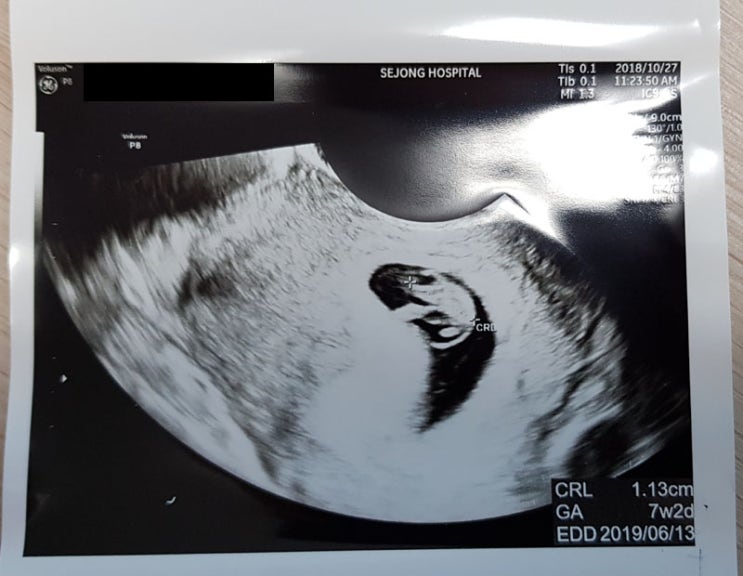

곰돌이와의 첫만남 20181027

부천의 세종병원에 산부인과 예약을 하고 방문을 하였다. 뭐 산부인과로 유명한 병원은 아니지만 있을만한 ...

곰돌이 Prologue

사실 블로그 글을 오랫동안 안쓴것도 있고... 회사일도 바쁘고 이사도 하고 너무나 바쁜일이 많았다. 하지...